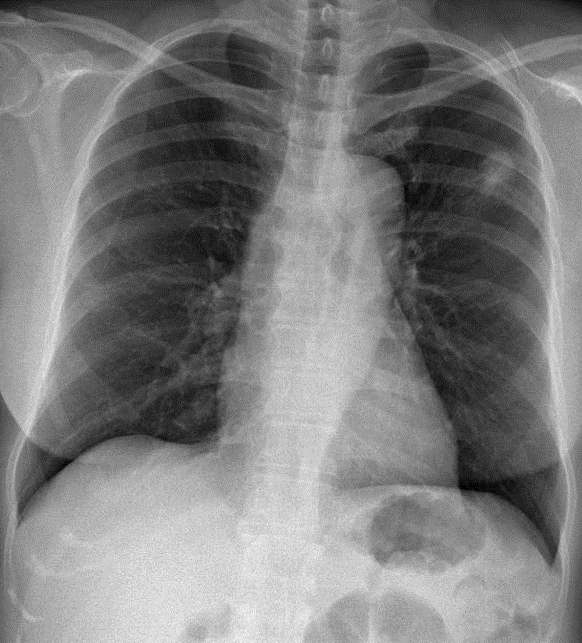

1-Nốt mờ thùy trên phổi (T) kèm thâm nhiễm vệ tinh xung quanh => U PHỔI (Tuberculoma, harmatoma, ...) 2-Đóng vôi sụn sườn trước hai bên